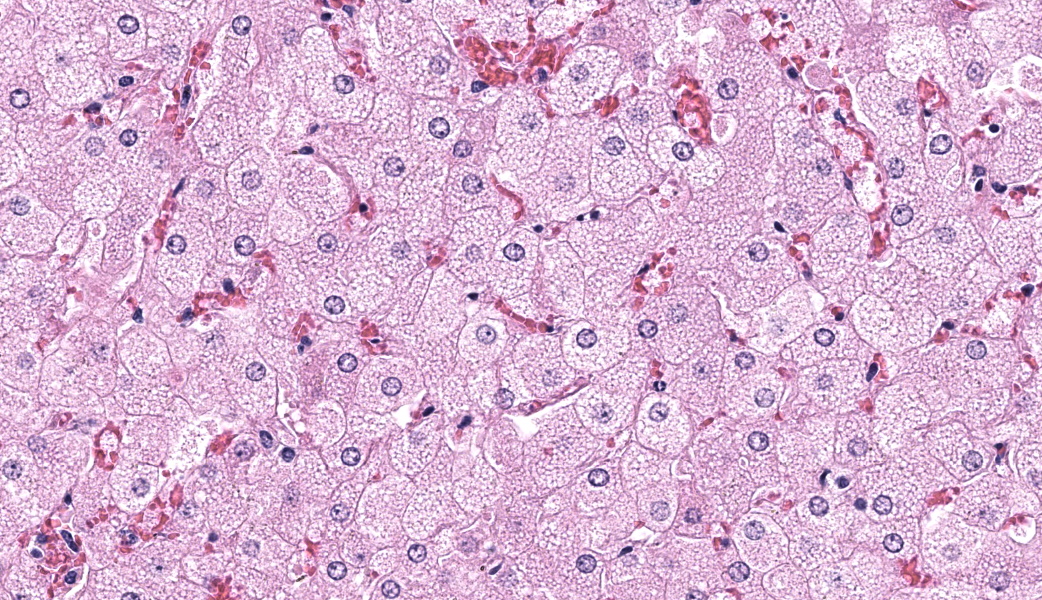

Microscopic Description:

Liver: Diffusely, hepatocytes are moderately swollen and contain numerous small (~1µm) discrete to coalescing cytoplasmic vacuoles (microvesicular hepatopathy). Nuclei remain centrally located. Within the centrilobular interstitium, hepatocytes are occasionally individualized, rounded, shrunken, and/or hypereosinophilic with karyolysis (necrosis). There is mild, patchy periportal hemorrhage.

Special stains:

Osmium tetroxide post-fixation revealed prominent staining of microvesicular lesions, confirming the vacuoles as lipid droplets.

Oil Red O revealed prominent staining of microvesicular lesions, again confirming the vacuoles as lipid droplets.

Contributor’s Morphologic Diagnoses:

Liver: Microvesicular hepatopathy, moderate, acute, diffuse, with mild centrilobular hepatocellular necrosis.